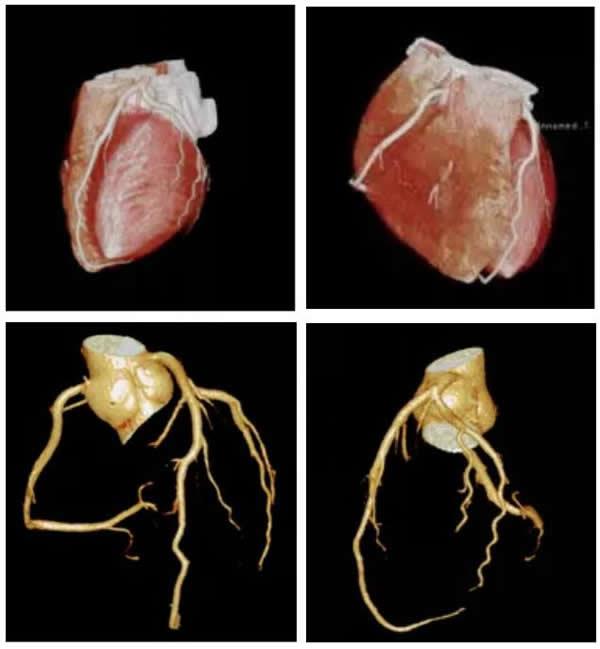

本站讯(通讯员 李冬冬 卢艳龙)为“心”护航,我们专心。12月26日,区首例心脏冠状动脉在区医共体医学影像分中心(台州市博爱医院影像中心)成像。

台州市博爱医院于今年引进路桥区首台64排/128层高端CT,率先在全区开展心脏冠状动脉CT(CCTA)成像。

博爱医院自推出“冠状动脉CTA志愿者招募”活动以来,引起社会的广大关注及强烈反响,报名人次远远超过预期。昨日,首批5名不明原因胸痛及可疑冠心病的患者接受了此项检查,短短数分钟即可显示高清逼真、恰如皇冠般的冠状动脉,经现场图像重建、阅片并出具国标诊断报告,为临床医生诊断及时提供了科学的依据。

据业内专家介绍,心脑血管疾病致死率高达42.6%,占我国死亡因素绝对第一位,尽早诊治是心血管疾病预后的关键。心脏冠状动脉CT血管成像以无创、快捷、价优、高准确性的优势在临床医学中已成为冠心病及不明原因胸痛的首选检查。